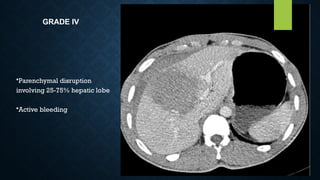

GRADE IV

•Parenchymal disruption

involving 25-75% hepatic lobe

•Active bleeding